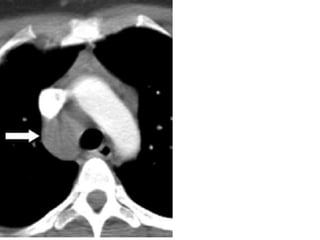

Chest CT scan

demonstrates an

anterior

mediastinal mass.

The anterior

junction line is

obliterated, where

as the lung

interfaces with the

hilar vessels

(arrow) and aorta

(arrowhead) are

preserved.

Chest CT scan demonstratesan anterior mediastinal mass. The anterior junction line is obliterated, where as the lung interfaces with the hilar vessels (arrow) and aorta (arrowhead) are preserved.